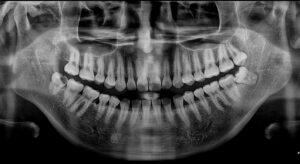

정밀한 검사를 위해

파노라마 사진을 촬영해 보았더니

아래턱 오른쪽 사랑니(#48) 외에도

왼쪽 위아래 사랑니(#28,38)도

맹출 되어 있는 상태로

구강 위생 관리가 잘되지 않고 있어

머지않아 아래턱 오른쪽 사랑니처럼

충치가 생길 가능성이 높은 상태였는데요.